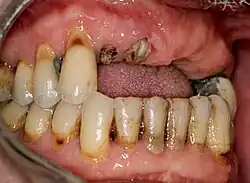

Partieller Zahnverlust der Zähne im Oberkiefer

Wurzelreste der Zähne 11, 12